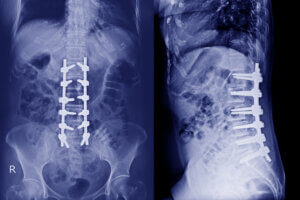

What an MRI Reveals That X-Rays Cannot

Traditional X-rays only show bones. They cannot show the soft tissues that are often responsible for back pain.

An MRI helps rule out conditions where decompression may not be appropriate, including:

-

Severe spinal instability

Advanced spinal stenosis

Fractures

Tumors or infections

Certain surgical complications

By identifying these issues early, an MRI helps ensure that patients receive the right treatment for their condition.